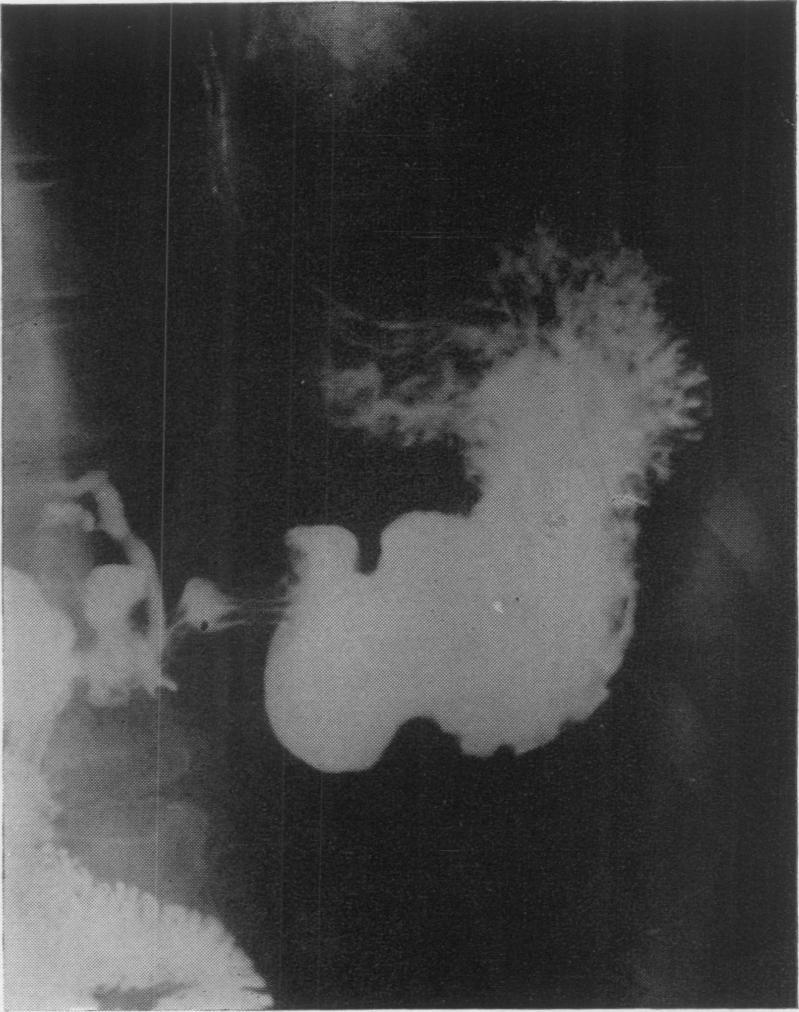

Choledochoduodenal fistula: its surgical management, including a report of three cases.

Ann Surg. 1954 Apr;139(4):510-6. doi: 10.1097/00000658-195404000-00018.